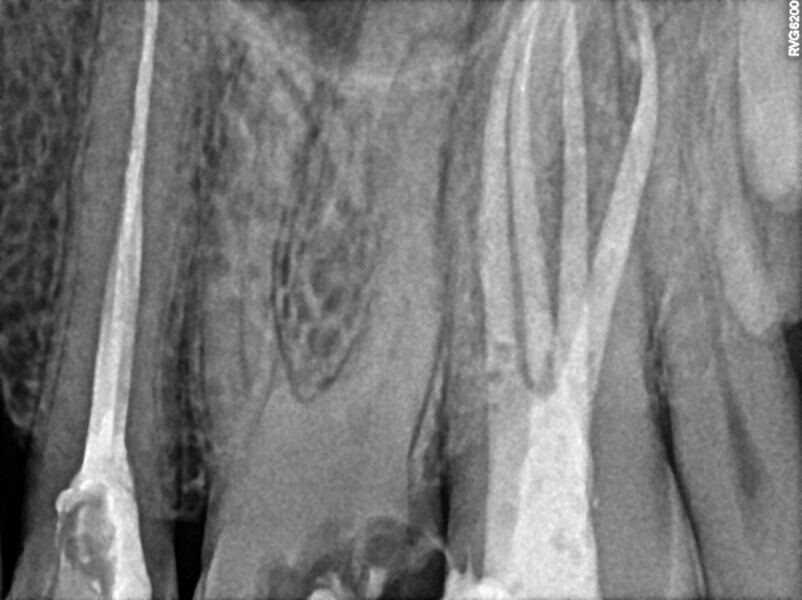

Post-op radiograph of a mandibular molar. (All Images: Bartłomiej Karaś)

Micro-CT scans allowed clinicians to improve their knowledge about the complexity of the root canal system. This kind of image can help the clinician to understand the network of blood vessels inside the roots, especially in the molars. Comparison of micro-CT scans with radiographs available on the internet reveals that there is a visible difference between the micro-CT scans and the postoperative radiographs regarding the quality of obturation. The most visible difference is in the area of the apical delta and isthmuses between the canals. This difference led us to deduce that, even though root canal therapy procedures are very successful, a great deal of root canal space is not cleaned of hard-tissue debris and filled with obturation material.

The in vitro trials and in vivo cases, periapical radiographs and postoperative CBCT images demonstrate that the laser activation of irrigants allows the clinician to achieve much better removal of the hard-tissue debris than with the conventional irrigation methods. The LPE concept appears promising in terms of the improved removal of hard-tissue debris. It is important to mention that this is only a clinical observation. The most important part of this observation is a very rapid flow of the irrigants between the root canals located in the same root after the LPE enhanced irrigation protocol with the SkyPulse laser but before apical preparation.

The LPE protocol is a modification of the classic root canal shaping and irrigation protocol and consists of two stages of irrigation and laser activation with SWEEPS technology. According to the postoperative periapical radiographs and CBCT images the number of isthmuses, lateral canals and portals of exit filled with sealer is visibly higher than after conventional protocols. This led us to hypothesise that the amount of hard-tissue debris, infected tissue and necrotic pulp removed is much higher than with conventional root canal therapy. It needs to be underlined that no research has yet been performed comparing the volume of removed hard-tissue debris between LPE and conventional root canal therapy. This concept requires further investigation to prove that this protocol can improve the success rate of root canal therapy.